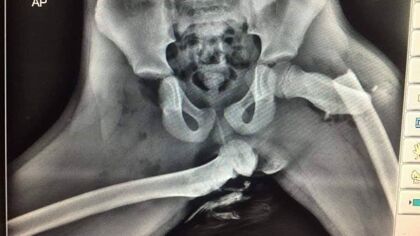

CuriosidadesEsta radiografía cuenta la devastadora historia de lo que puede sucederles a aquellas personas que viajan con los pies apoyados sobre el salpicadero.